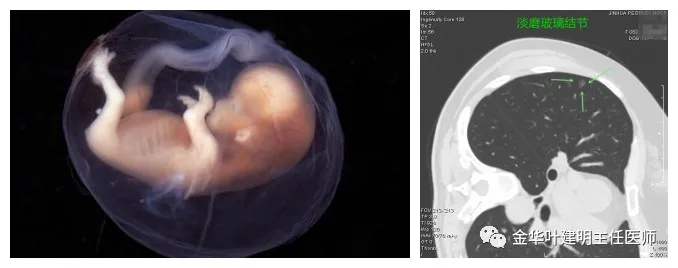

不典型增生:多像他还是个胎儿,仍在母体内,能不能顺利降生都还是未知数,对外侧根本没有破坏力;影像上只表现为淡磨玻璃结节,没有风险,随访观察不影响健康,也可能永远长不大(胎死腹中),若顺利降生,仍会经历非常容易控制的婴幼儿阶段。